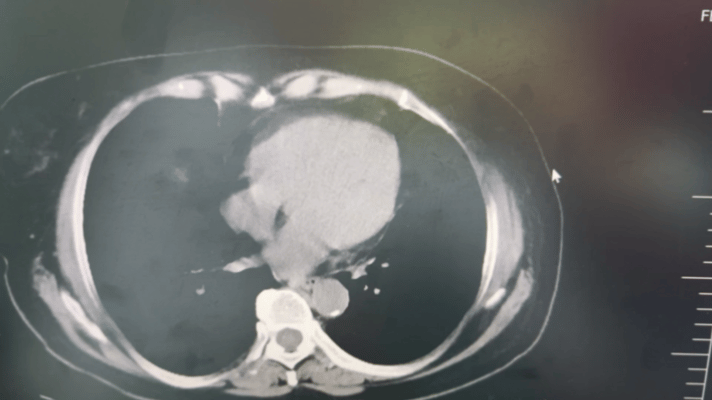

患者近半年来一直被腹胀和餐后呃逆所困扰,胸闷憋喘、 活动受限,持续的不适感严重影响了她的生活质量。随着症状的逐渐加重,患者决定寻求专业医疗帮助。患者来院后,经上腹部CT检查,明确诊断为“肝脏、双肾盂多发囊肿”及“胆囊结石”。面对这一诊断结果,患者决定在我院接受进一步治疗。